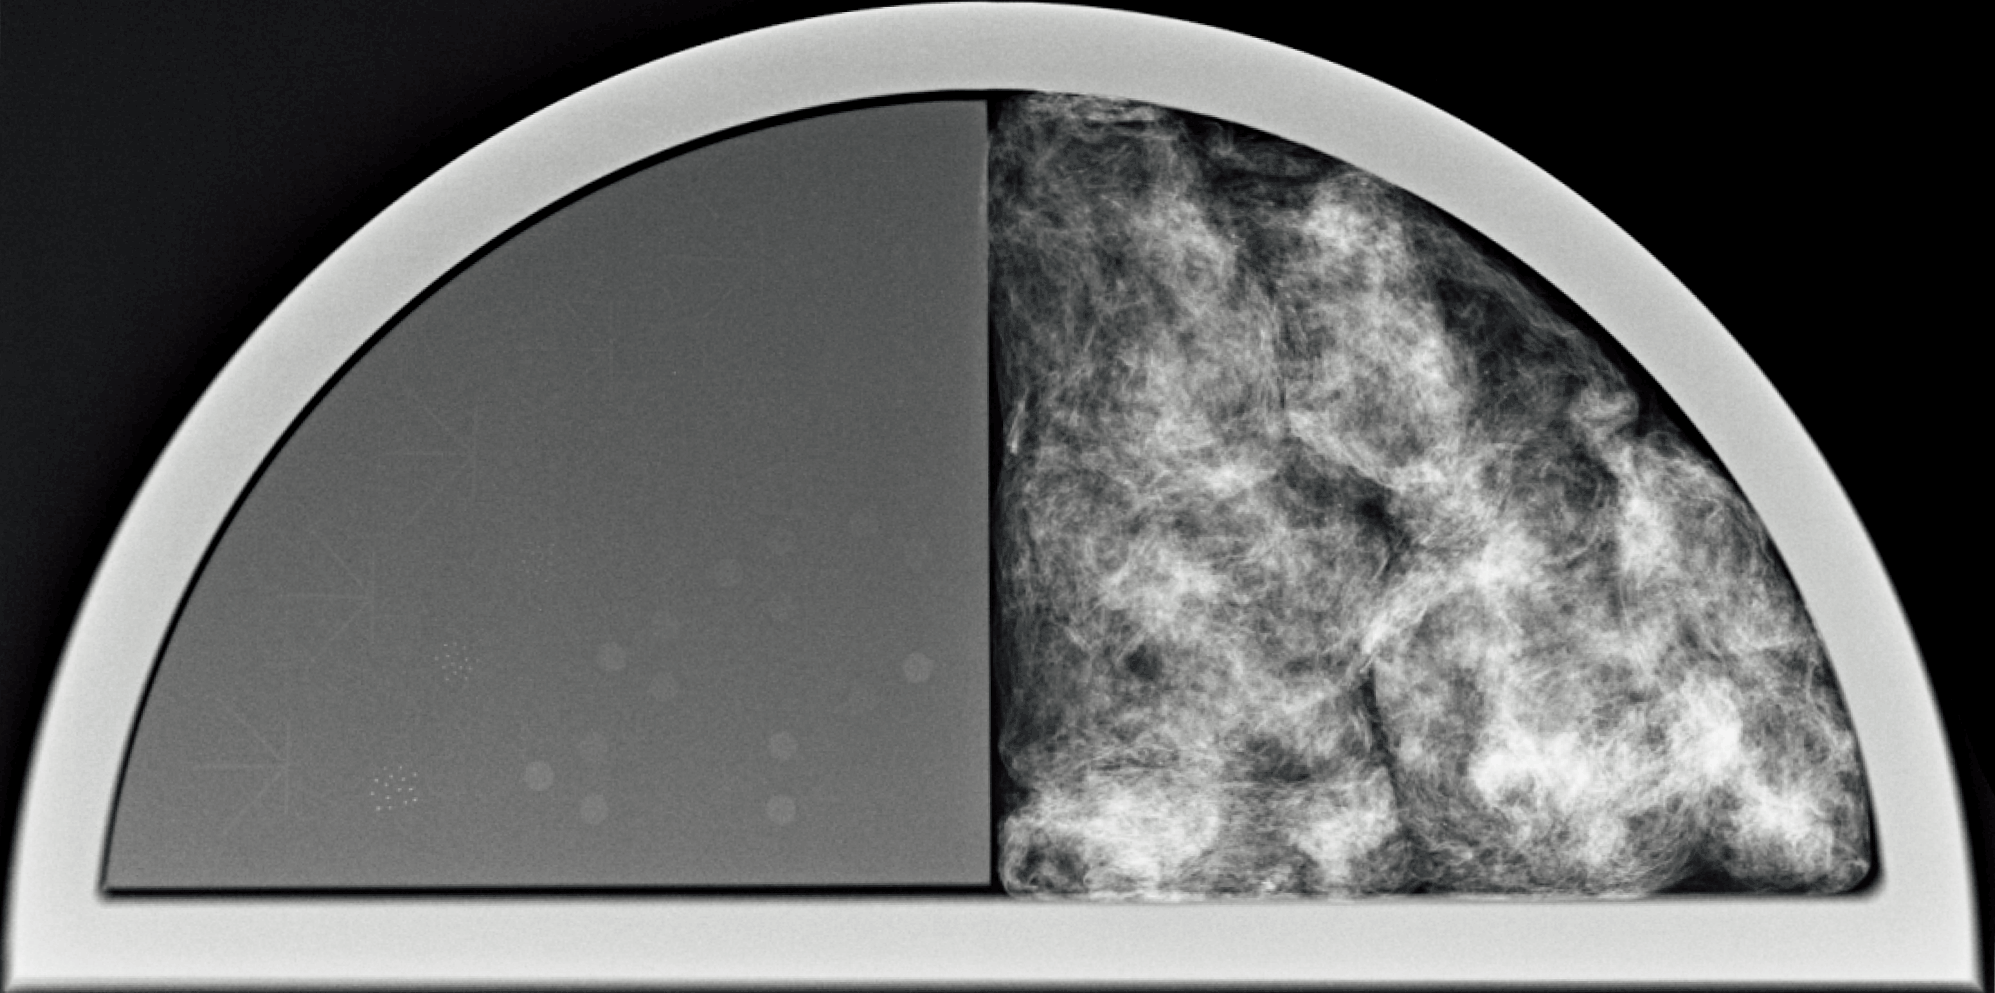

TOR MAM マンモグラフィ ファントム の半分には、フィラメント、微粒子、低コントラストの細部が含まれており、

それぞれ棘状突起、微小石灰化、腫瘤を模擬しています。これらを用いて画質スコアを得られます。

また、もう半分には乳腺組織の外観をシミュレートし、線維や結節の細部に加えて微小石灰化を含んでいます。